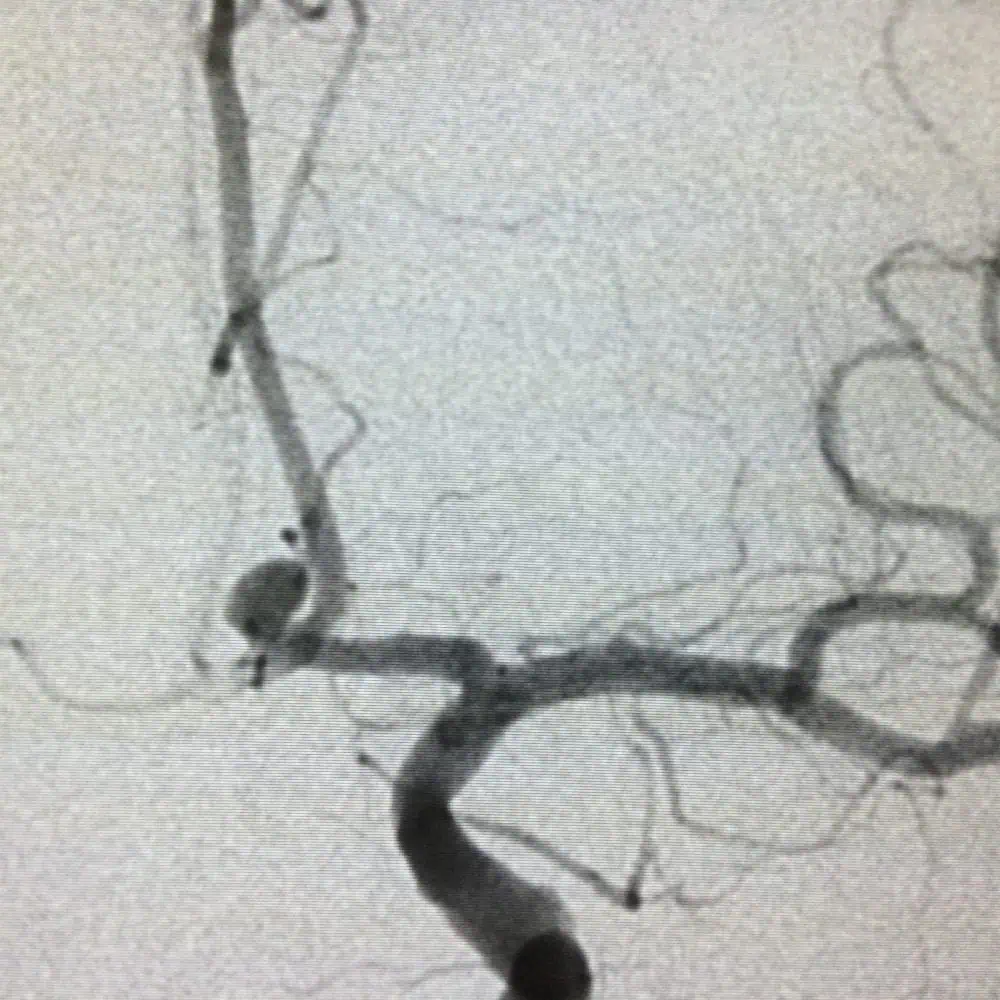

Революционното е, че освен с инжекции, които разтварят съсиреците, вече може, както правят кардиолозите, да се стига до мозъчните артерии. Там се влива вещество, което по химически път разтваря тромба, или механично се изтегля със стент. Скъпичко е, защото един флакон от препарат за разтваряне на съсирека струва 900 лв., а са нужни два за ефективно лечение на един човек. Заплаща се от болницата, не от пациента.